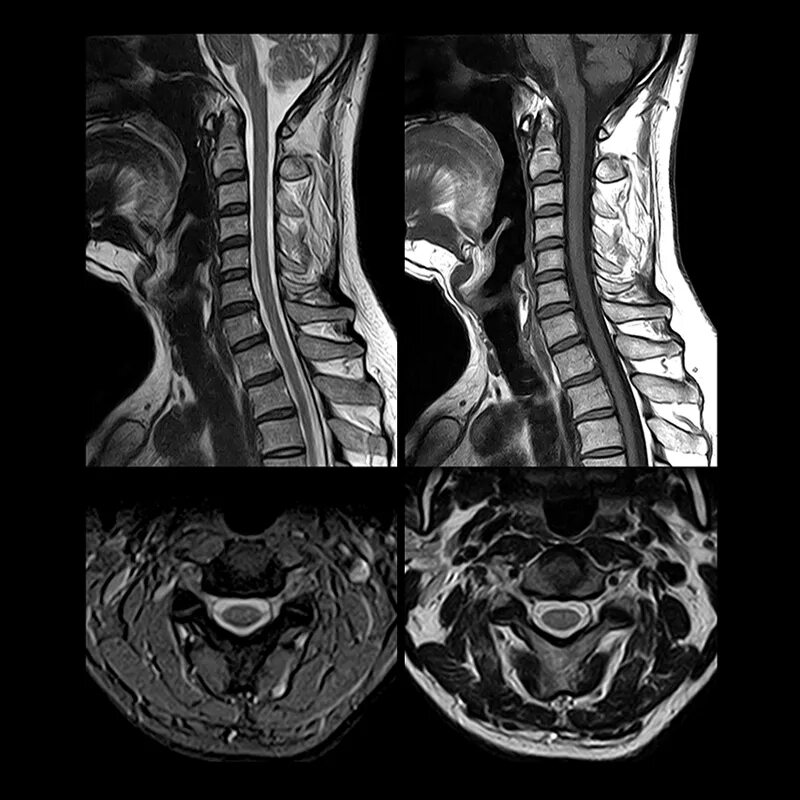

Чем отличается кт от мрт поясничного отдела